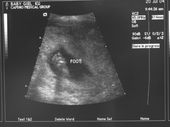

Ultrasounds

IT'S A GIRL!!! Here are the ultrasound scans. She is now 5-6" crown to rump (head to butt) My favorite pictures are of the foot and the one where she is sucking on her thumb.